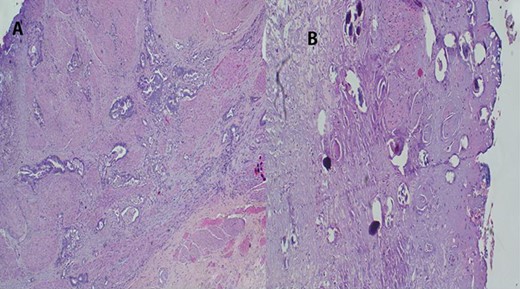

(A) Histopathology of colon with adenocarcinoma associated with Schistosoma ova with poorly formed granulomatous inflammation, hematoxylin and eosin (H&E) ×20 magnification. (B) Adenocarcinoma and Schistosoma ova with dense lymphocytic infiltrates ×40 magnification.

The report revealed a segment of colon with low-grade invasive adenocarcinoma (pT3NxM1) and Schistosoma eggs embedded in the tumor (Fig. 3).